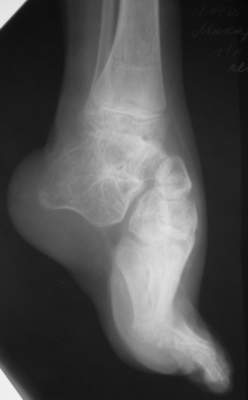

в 4 года оперирован у нас - операция по типу Зацепина, далее аппарат Илизарова... Предоперционная картина - как на рис "case 1 a" (фото другого больного)... При операции использовался аппарат с "моноблоком" стопы - см. "case 1 b" (фото другого больного) - в связи с чем интраоперационно провели достаточно выраженную одномоментную коррекцию после чего возник некроз в области операционных ран в результате чего "вывалился" "кусок" по внутренней поверхностих... аппарат сняли... больного перевели в отделение микрохирургии... с другой голени делали пересадку... прижилось... больного выписали... все это было 7 лет назад... 3 года назад больной лечился в Астрахани... Никаких выписок нет (не видел...) (хэллоу, астраханцы!!! если есть - отзовитесь...), но со слов мальчика и его матери ему делали удлинение на уровне верхней трети голени плюс исправляли стопу... опять-таки со слов - сразу же после коррекции стопу загипсовали на 6 нед, после чего прописали ночные тутора плюс ортообувь... т.е. после коррекции стопу в аппарате не выдерживали и гипсовали всего 1,5 мес.... через 6 мес стопа "ушла" в исходное положение... с которой он пришел к нам сейчас... (case 2-9) В настоящее время у мальчика эквино (!!!)-варус... в подтаранном суставе полный анкилоз... (см. Ro) Были предложения исправить деформацию аппаратно с остеотомией через ладью... Передумали :-) ... Лично у меня возникают также вопросы на счет плюсне-клиновидных сусутавов... и так я их Ro-фировал, и эдак (снимки не представлены), а все равно не могу избавиться от впечталения, что и в них имеется некое фиброзно-костное анкилозирование... А на КТ у больных денег нету... Короче... Наложили аппарат... Попытаемся растянуть стопу + "подкоррегировать" варус и убрать эквинус... А после этого определиться с уровнем остеотомии (это официальное мнение...) Я же хочу сделать все тоже, за исключением остеотомии (при условии что нет того самого анкилозирования на уровне плюсне-клиновидных сусутавов...) Убрать варус и эквинус на фоне удлинения... коррекция с гипер-... плюс подержать в этом положении 1-1,5 мес... Но не лежит рука к остеотомии... Единственное, после коррекции есть желание "отсепарировать" подошвенные связки с костной "основой" от пяточной кости и загипсовать в таком положении во избежание возможного рецидива... А там посмотрим... мнения ???